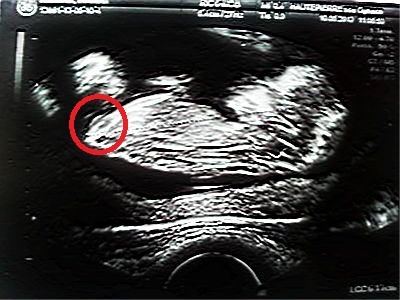

je vous met quand même ma photo avec le filtre :P

je suis pas myope mais je vous assure je vois quelque chose qui dépasse

d'après l'écho vu ce que je vois moi ça descend, et donc si le tubercule ne monte sa pourrait être une nenette!